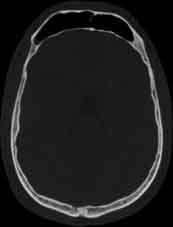

Visible Human male: Sectio transversalis 1074

CT